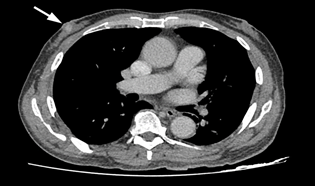

A 72 years old gentleman presented to our centre in 2019 with the right breast swelling and painless nipple bloody discharge for the past three months. He claimed the swelling was progressively increasing in size with changes noted on the surface of the nipple skin. The patient also had constitutional symptoms such as loss of weight and loss of appetite for the past one year. He claimed he lost about 10kgs in the last 6 months. Otherwise, the patient denies having any family history of breast cancer nor consumed any kinds of hormonal pills or supplements. Triple assessment was done on the patient and clinical examination revealed a hard, non-tender lump at the retro areolar region measuring about (2x1) cm. There were blood and serous discharge from the nipple. No mass was palpable on the other region of the breast or contralateral side. Bilateral axillary lymph nodes were not palpable. Initial right breast ultrasound noted the presence of cystic and solid lump at the retro areolar region measuring (1x1x1.8) cm. Also noted was internal vascularity with a layer of sediment within the cystic mass. The imaging findings were categorized as BIRADS 4.We then proceed with computed tomography (CT) scan and noted the presence of a focal enhancing retro areolar lesion on the right breast measuring (0.8x0.8x1.0) cm with no extension to the underlying structures. There were some sub-centimetres bilateral axillary lymph nodes with preserved fatty hilum with largest was 0.9cm in the right axilla. Ultrasound-guided biopsy was performed and was confirmed to be of intra-ductal papillary carcinoma in origin. The patient was staged as T1N0M1 according to the TNM classification. The patient was arranged for a right mastectomy the following week. He was then discharged home well after a week and a surveillance mammogram was performed a year later and no focal lesion seen on the left breast (Figure 1 & 2).

Figure 1 Ultrasound image of the right breast showing a mixed solid cystic lesion with microlobulated border at the retro-areolar region.

Figure 2 CT scan image axial view showing a focal enhancing lesion at the right retro-areolar region with no extension to the underlying pectoralis major muscle.